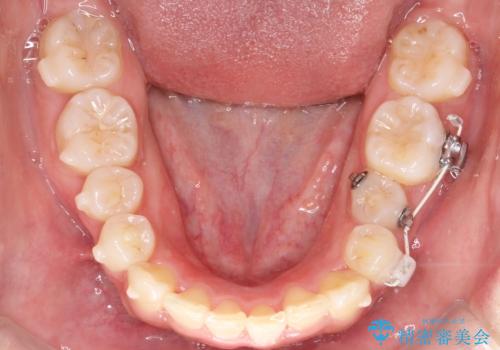

- 歯のデコボコ(叢生)を気にされて来院されました。精密な検査の結果、中等度の叢生と診断。患者様のご希望に合わせ、透明で目立ちにくい**インビザライン(マウスピース矯正)**による治療計画を立案しました。歯を抜かずに、歯列弓(歯が並ぶアーチ)を少しずつ拡大することで、歯が並ぶスペースを確保し、叢生を改善することを目指します。

今回の矯正治療では、透明なマウスピース型の装置インビザラインを使用しました。この装置は目立ちにくく、取り外しが可能なため、食事や歯磨きも普段通りに行えます。治療は、緻密に計算された治療計画に基づき、段階的に作製されたマウスピースを交換していくことで、歯列弓全体を徐々に広げていきました。この歯列弓の拡大により、不足していたスペースを確保し、歯のデコボコを効果的に解消。抜歯することなく、整った美しい歯並びと良好な咬み合わせを獲得していただけました。